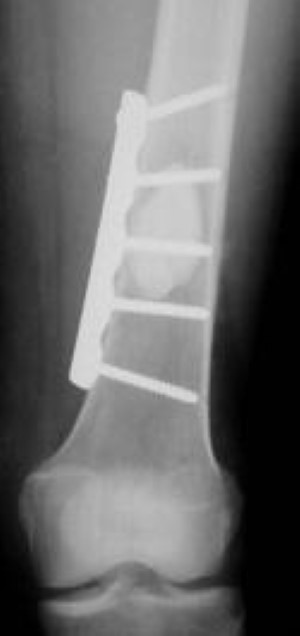

plate and screw fixation of distal femur for MBD

In this X-ray, the weakened lower end of the femur has been stabilized with a plate and screws. In this case, plate-and-screw fixation will maintain stability and allow the patient to bear weight on the leg.

Distal Femoral (Supracondylar)

Lower end femur (supracondylar) lesions can be a challenge to treat secondary to multiple bone fragments and poor bone quality. Generally, you can obtain good function with a metallic implant, but when the bone is badly destroyed, the end of the femur and the knee may need to be replaced. This form of knee replacement is usually more involved than the knee replacement procedures for arthritis.